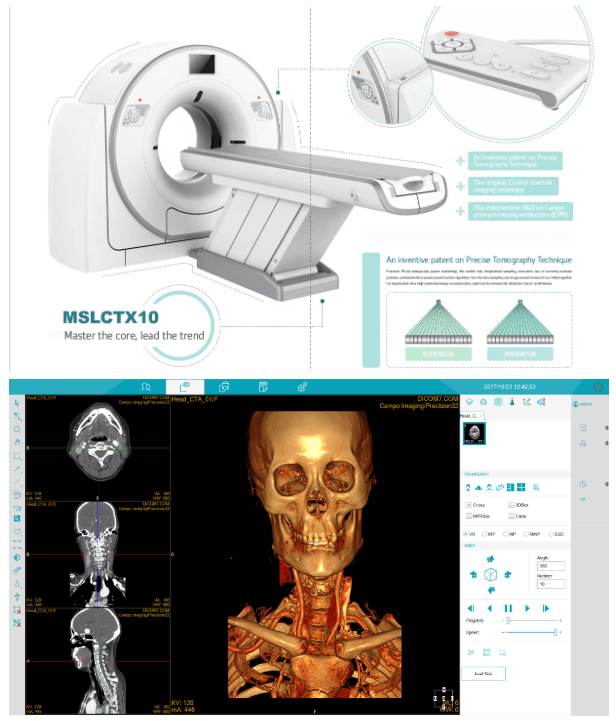

Spiral-CT

The product overview of x ray mri ct scanner 32 slice spiral ct scan machine for human

MSLCTX10 CT system is completely developed by Campo Imaging. It is the first CT product of Campo Image. P-Axial is a patent of MSLXTX10 CT system. It can obtain the thinnest CT images in the 0.275mm and has obvious advantages in the application of inner ear imaging and pulmonary nodule detection. 32-slice dual energy imaging extended the application of CT dual energy imaging. MSLXTX10 CT system provides high quality images and stable performance which can help hospitals to achieve comprehensive accurate diagnosis, and it will redefine the new standards of 32-slice CT imaging.